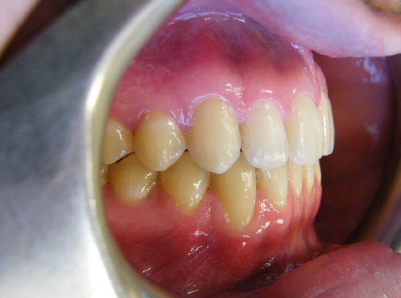

Patient 2: Significant increased overjet and upper and lower crowding.